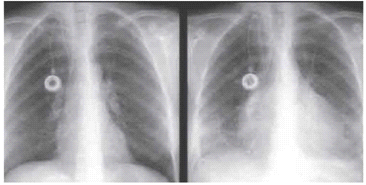

ניסיונות להגיע לאבחנה על סמך אק"ג, צילום חזה או דופק פרדוקסלי נכשלים על פי רוב. באק"ג ניתן לראות שינויים בלתי ספציפיים בסגמנט ST ושינויים בגלי T. הסימנים באק"ג יכולים להיות מאוחרים ולכן אק"ג תקין אינו שולל חבלה בלב. בדיקת האנזימים מסוג של CPK-SGOT, LDH אינה אבחנתית, מכיוון שהם עולים בכל חבלה שרירית. עלייה באיזואנזים לבבי של CPK או של טרופונין יכולה להצביע על חבלה בלב. בצילום חזה נראה את צל הלב מוגדל מאוד. תמונה זו תופיע רק לאחר שבפריקרד ימצאו כ-250 סמ"ק דם שדלף. בנוסף, בשיקוף חזה ניתן לראות שאין שינוי בצל הלב בזמן נשימה או שאיפה ממצא המעיד על נוזל רב בפריקרד (תצלום 17.16). פריקרדיוצינטזה (דיקור הפריקרד ושאיבת נוזל מתוכו – איור 13.16) נושא שיעור משמעותי של תוצאות כוזבות, שליליות או חיוביות. הסיבה העיקרית לתוצאה שהיא כוזבת שלילית היא התהוות קרישים בפריקרד במצבים של טמפונדה חדה. הקרישים מונעים שאיבה באמצעות מחט. תיתכן תוצאה כוזבת חיובית כאשר המחט חודרת לחלל הלב עצמו. אין מקום לשימוש בפריקרדיוצינטזה כטיפול במרכז טראומה, שבו קיים חדר ניתוח זמין והעברת הפצוע מתבצעת תוך דקות. פריקרדיוצינטזה יכולה לשמש ככלי אבחנתי וכטיפול ראשוני בפצועים עם חשד לפגיעה חודרנית בלב, הנמצאים במקום מרוחק מהמרכז הרפואי, שבו ניתן להתמודד עם פציעות מסוג זה.